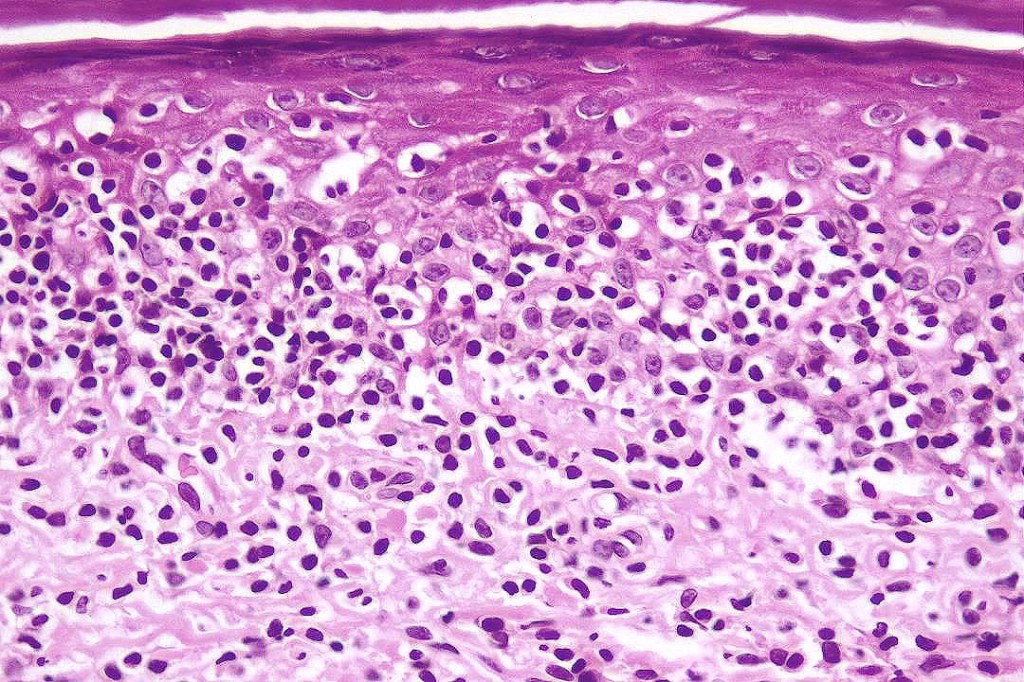

•Very marked epidermotropic infiltrate of atypical lymphocytes including Sézary cells

•Perinuclear halo often present

•Pautrier-like microabscesses

•Superficial dermal perivascular lymphohistiocytic infiltrate with only sparse or absent atypical forms